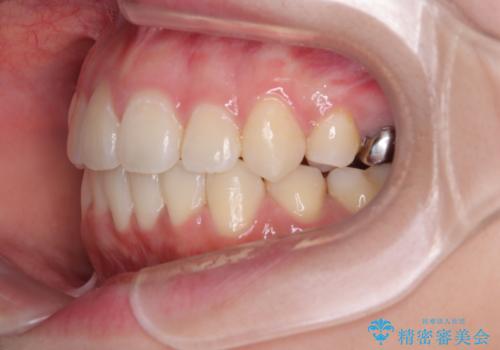

- 下の前歯のデコボコと、口元の突出感を改善したいと来院された患者様です。

突出感の強い上顎前歯をしっかりと後方移動させるため、上顎の裏側の補助装置(リンガルアーチ)とアンカースクリューを併用しています。

上下左右の第一小臼歯を抜歯して、目立ちにくいワイヤー装置で矯正を行いました。

上下の保定用マウスピースの他に、デコボコの強かった下顎前歯にはワイヤーで保定をしています。